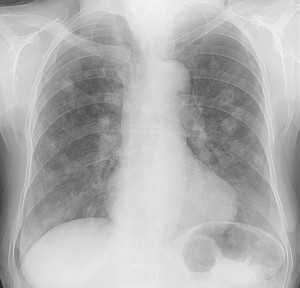

Метастазы в легких — фото рентгенограммы. Округлые тени — метастазы рака пищевода. Хорошо виден большой узел округлой формы вблизи переднего отрезка 2-го ребра. На снимке справа - циркулярное сужение пищевода за счет опухолевого утолщения его слизистой оболочки.

Как выглядят метастазы в легких на рентгене? Слева — узловые образования у пациента с раком яичка. Справа - метастазы рака яичников гематогенного характера с выраженным опухолевым лимфангиитом (обратите внимание на деформированный сетчатый, линейный характер легочного рисунка).